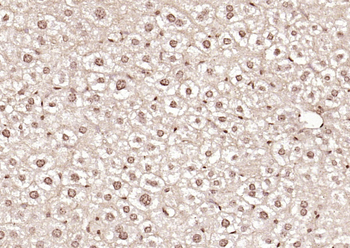

50 μl, 100 μl - MARK3 Recombinant Rabbit Monoclonal Antibody [orb704310]Featured

ICC, IF, IHC-Fr, IHC-P

Human, Mouse

Rat

Rabbit

Recombinant

Unconjugated

50 μl, 100 μl - Featured